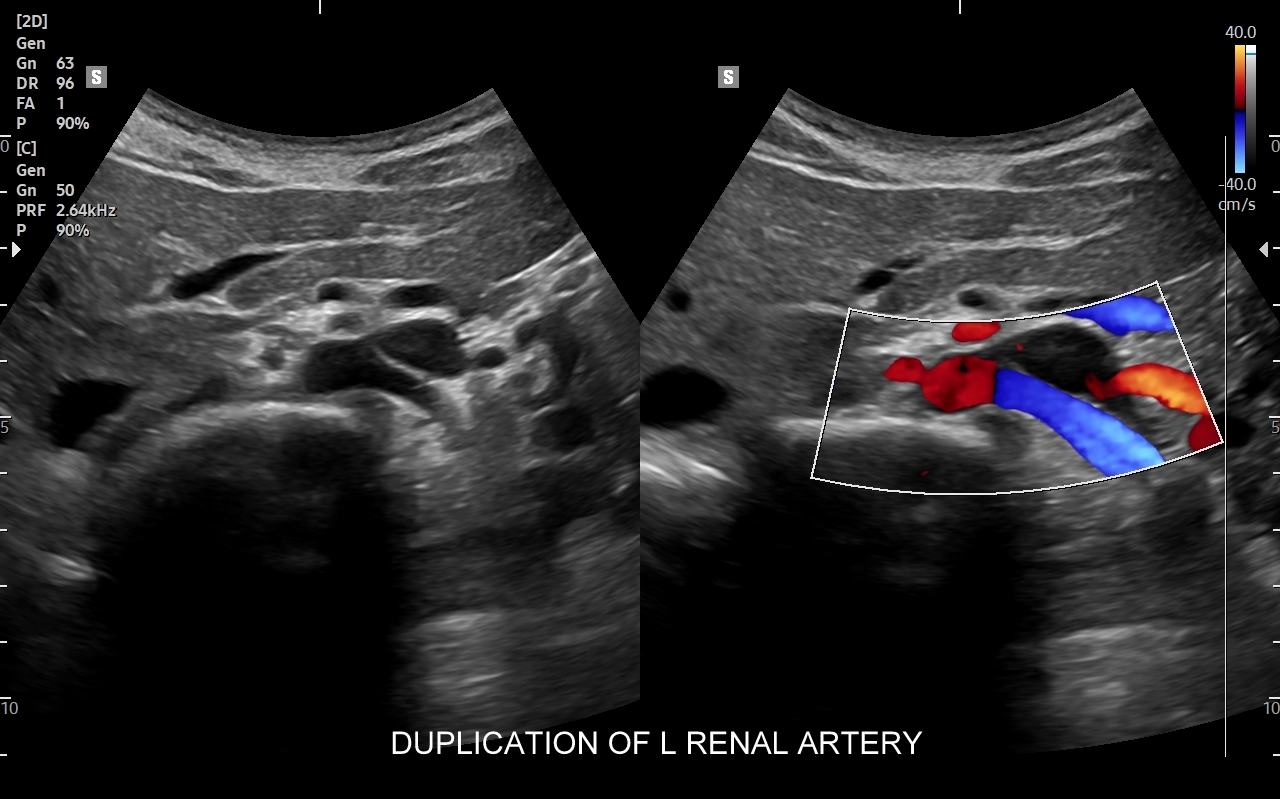

Badanie multiparametryczne MPUS jamy brzusznej

Rozwinięciem standardowego badania USG jamy brzusznej jest badanie multiparametryczne MPUS (ang. multiparametric ultrasound), w ramach którego wykorzystuje się różnorodne, nowoczesne modalności sonograficzne, takie jak tryby mikrounaczynienia MVI, B-flow, elastografię, ilościową ocenę stłuszczenia wątroby QUS, czy tryb Dopplera spektralnego, a to wszystko w celu uzyskania dodatkowej oceny funkcjonalnej i biologicznej struktur, narządów oraz tkanek jamy brzusznej. Obrazowanie MPUS niejednokrotnie poprawia także wizualną ocenę narządów wewnętrznych, czego przykładem jest zastosowanie trybu MVI w ramach bezkontrastowej angiografii sonograficznej naczyń oraz w ocenie guzów nerek. Klasycznymi i najczęstszymi zastosowaniami badania MPUS są jednakże funkcjonalna ocena wątroby w kierunku stłuszczenia, zwłóknienia, zapalenia i nadciśnienia wrotnego, a także ocena żywotności i funkcji nerek.

• Możliwość rozszerzenia zakresu badania USG w razie wystąpienia konieczności. Praktycznymi przykładami są zastosowanie trybu MVI w przypadku wykrycia guzka w nerce, czy przeprowadzenie badania elastograficznego i dopplerowskiego w wypadku stwierdzenia nieprawidłowego obrazu wątroby.